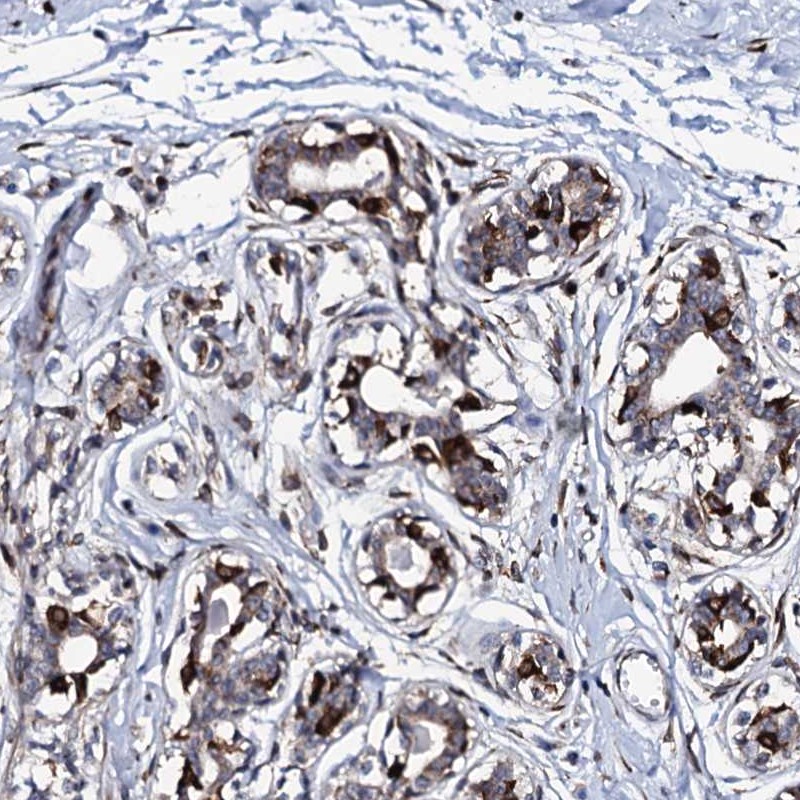

Immunohistochemical staining of human breast shows strong positivity in a subset of glandular cells.